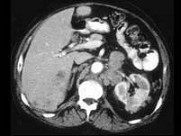

- 多项选择题男,54岁, 左侧腰痛,伴间歇性血尿2个月余, 结合所示图像,下列哪项描述正确 ( )

A、左侧肾癌

B、肝内多发转移癌

C、肝癌

D、左肾转移癌

E、腹主动脉旁及左肾门区淋巴结转移